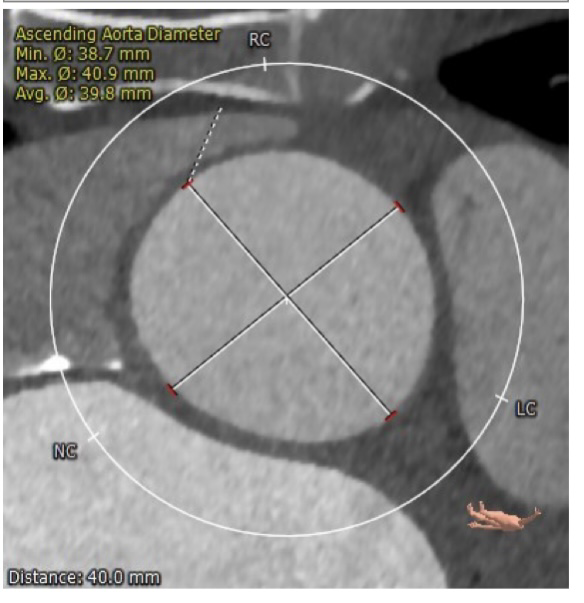

CTA主动脉根部解剖:患者为二叶瓣,重度钙化,瓣环平面可见钙化,可见钙化延伸至左室流出道,右无、左无均可见融合,以右无融合为明显,冠脉高度尚可。升主动脉最宽处为超过 45mm,心脏角度约:49度。

升主最宽处:39.8mm